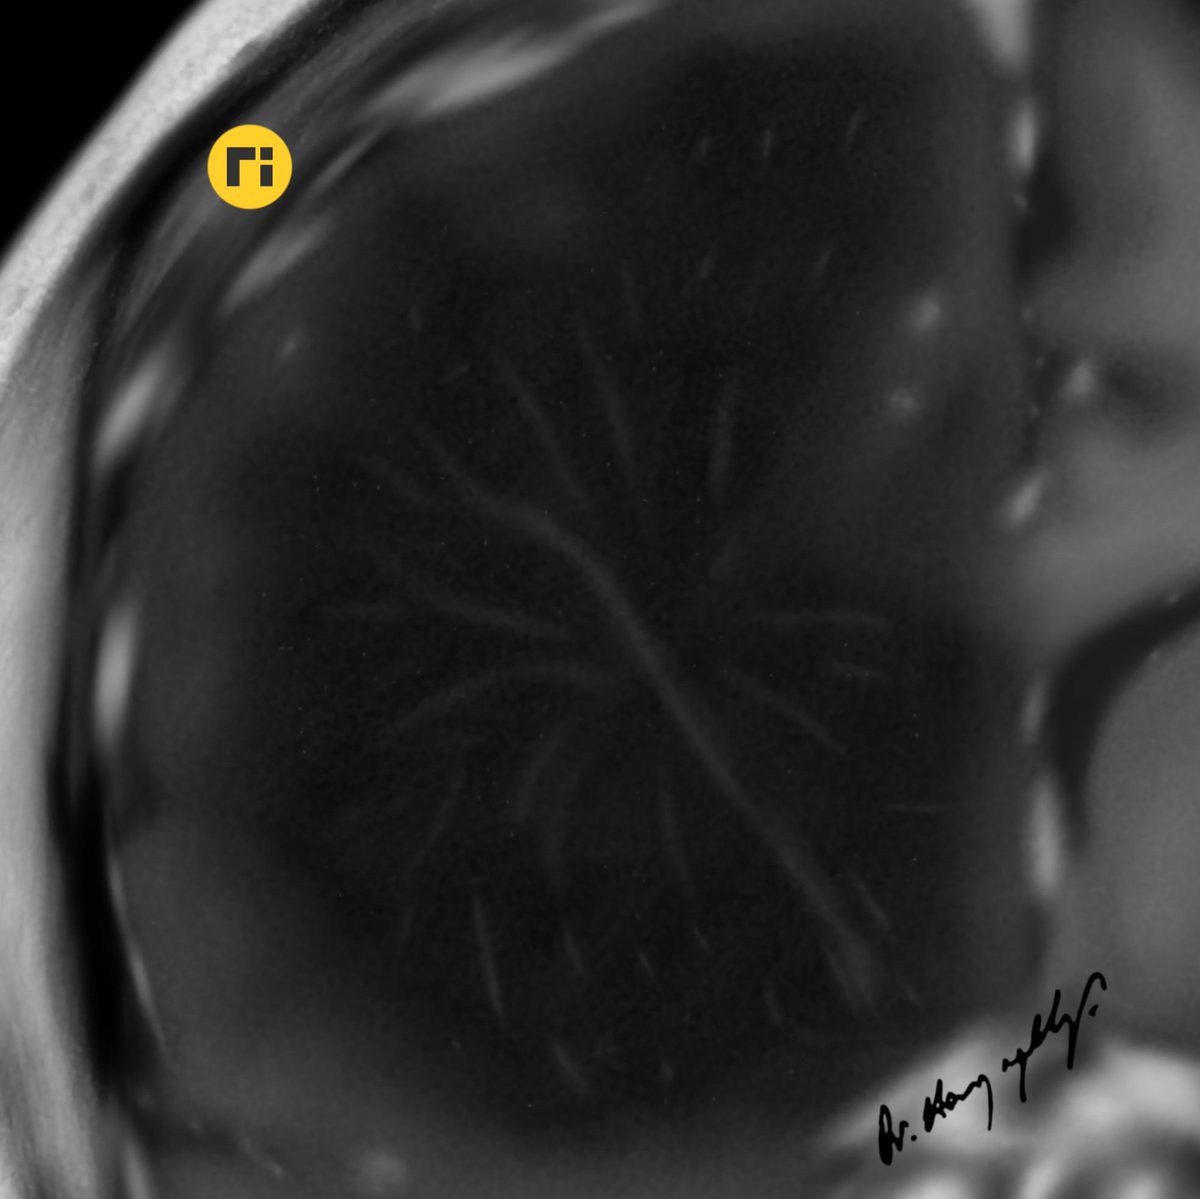

Fresh! 👍♥️🙋‍♂️ Imaging patterns of paediatric CNS mitochondrial disorders https://t.co/M3ohYWjbLW #radiologicalillustration ✍️ pixel by pixel handmade!

“Fireworks Sign” Diffuse Astrocytoma (MYB or MYBL1-altered) https://t.co/oxgM0KUy5T #radiologicalillustration ✍️ pixel by pixel handmade!

Dilated Perivascular Space https://t.co/42DZ2C2qEQ #radiologicalillustration ✍️ pixel by pixel handmade!